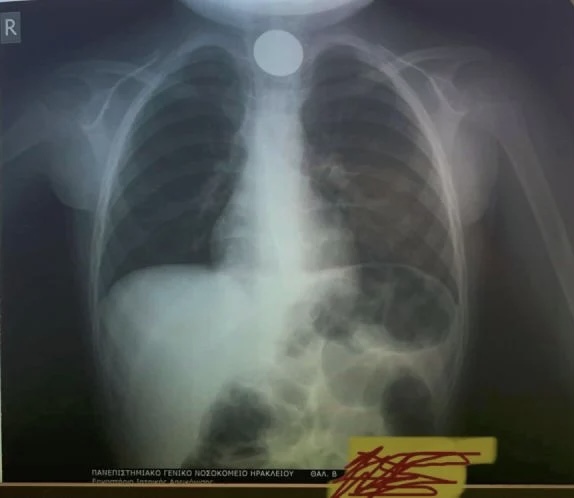

Η κλινική ΩΡΛ του νοσοκομείου έκανε και σχετική ανάρτηση, συνοδευόμενη από φωτογραφία της ακτινογραφίας θώρακος που έγινε στο παιδάκι και στην οποία φαίνεται ξεκάθαρα το κέρμα!